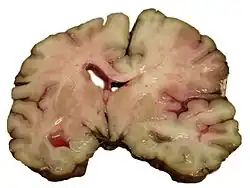

![]() | |

| CT scan of the brain showing a massive, prior right-sided ischemic stroke from blockage of an artery. Changes on a CT may not be visible early on.[1] | |